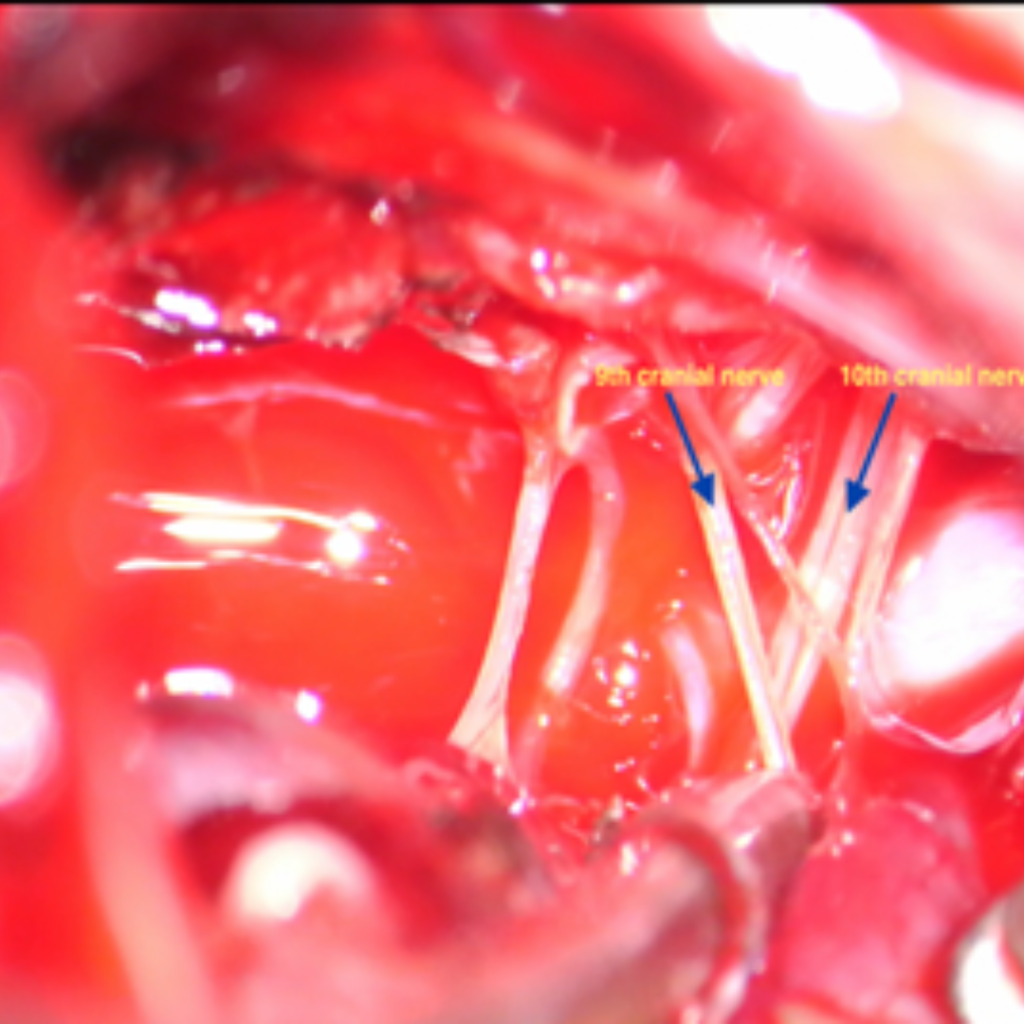

1. 9th: Glossopharyngeal

2. 10th: Vagus

Schwannoma arising from any nerve impair function of that nerve. As lower cranial nerves helps in swallowing movements ,patients having lower cranial nerve schwannoma present with swallowing difficulty , nasal regurgitation, cough while drinking water.As tumor size increases it compresses brainstem, cerebellum leading patient to have swaying while walking , difficulty in balancing .

Main aim of surgery is maximum safe resection while preserving the function of involved nerves. Ideally it is done under Neuromonitoring of involved nerves. Sometime it may not be possible to identify and separate nerve from tumor. In that case patient may face difficulty in swallowing , nasal regurgitation while drinking or repeated salivary micro aspiration into lungs leading to pneumonia. To avoid this, temporary tracheostomy may be required. Patient may have to put on ryles tube( tube through nose) to feed for shorter duration which may get prolong in case of non-improvement.

Lower Cranial nerves entering jugular fossa